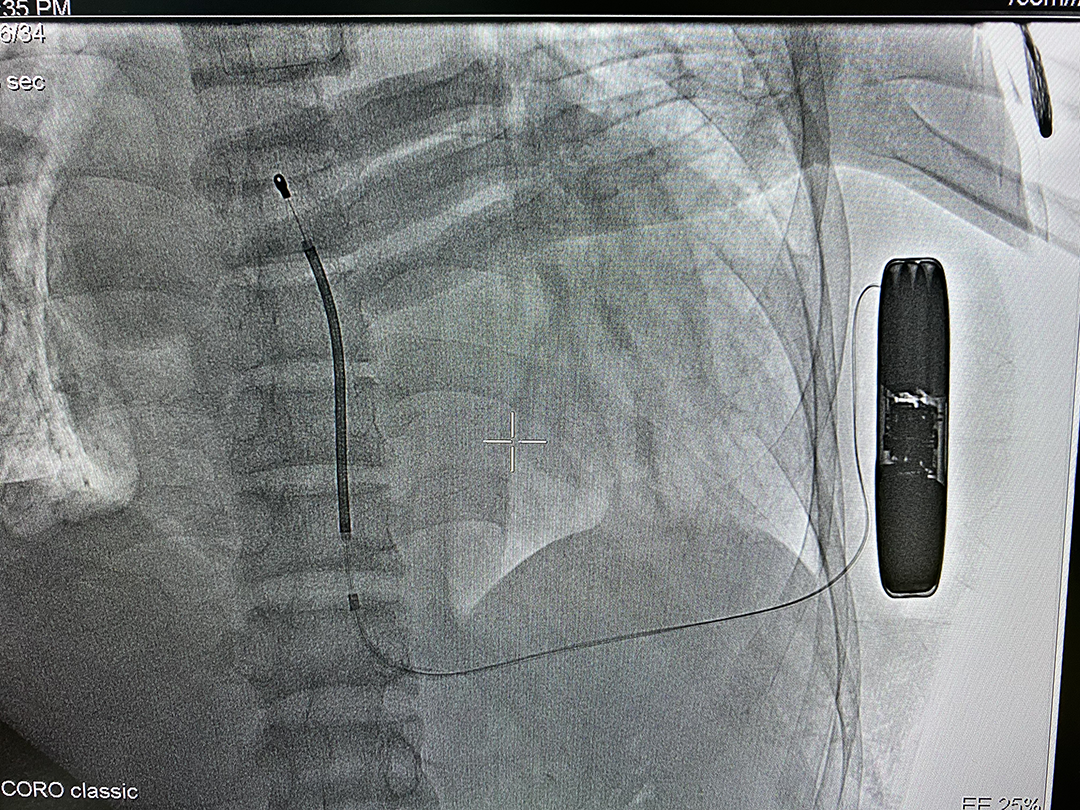

2022年6月17日,由中山大学附属第五医院心律失常科王欢主任团队独立地为一位年轻的心脏性猝死一级预防的患者成功植入本院首例皮下植入式心律转复除颤器(S-ICD),术程顺利。

接受本次S-ICD植入手术的患者是一名41岁男性,因“尿毒症性心肌病、扩心病待排,心功能III級;频发室性性早搏、短阵室性心动过速;慢性肾脏病CKD5期”,收住入院。经系列辅助检查,该病例特点有:(1)尿毒性心肌病;(2)频发室性早搏,彩超显示全心扩大,LVEF20%,属于1.5级预防;(3)无起搏需求;(4)慢性肾脏病CKD5期,左侧血管造瘘,长期血液透析。

根据术前评估和猝死预防相关的最新指南,该患者属于猝死极高危人群。因患者感染风险高、预期寿命长,且无起搏需求,有对日常生活影响小等诉求,为避免传统经静脉置入ICD可能导致的血管并发症风险及心室除颤电极可能导致的相关并发症及提升患者日常生活质量和满意度,经过与患者及家属充分沟通,王主任为患者选用了目前全球唯一可兼容核磁全身扫描检查的皮下植入式除颤器(S-ICD)。

LL